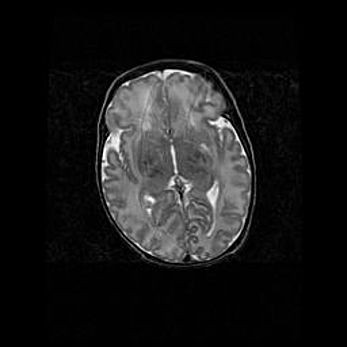

Сообщающаяся гидроцефалия. Кистозная энцефаломаляция головного мозга.

Возраст: 3 месяца 4 дня

Вес: 3100 г

Пол: женский

Окружность головы: 34 см

Срок гестации: 31 неделя

Кистозная энцефаломаляция головного мозга - одна из форм поражения головного мозга в детском возрасте. Характеризуется возникновением множественных и распространённых кист в коре, белом веществе и подкорковых образованиях головного мозга у плодов, новорождённых и детей раннего возраста. Развитие кистозной энцефаломаляции связано с внутриутробной асфиксией и гипотонией, родовой травмой, тромбозом синусов, пороками развития сосудов, инфекциями, сепсисом и другими причинами. Наиболее значимые инфекционные агенты: вирусы простого герпеса, цитомегалии, краснухи, токсоплазмы, энтеробактерии, золотистый стафилококк и другие.